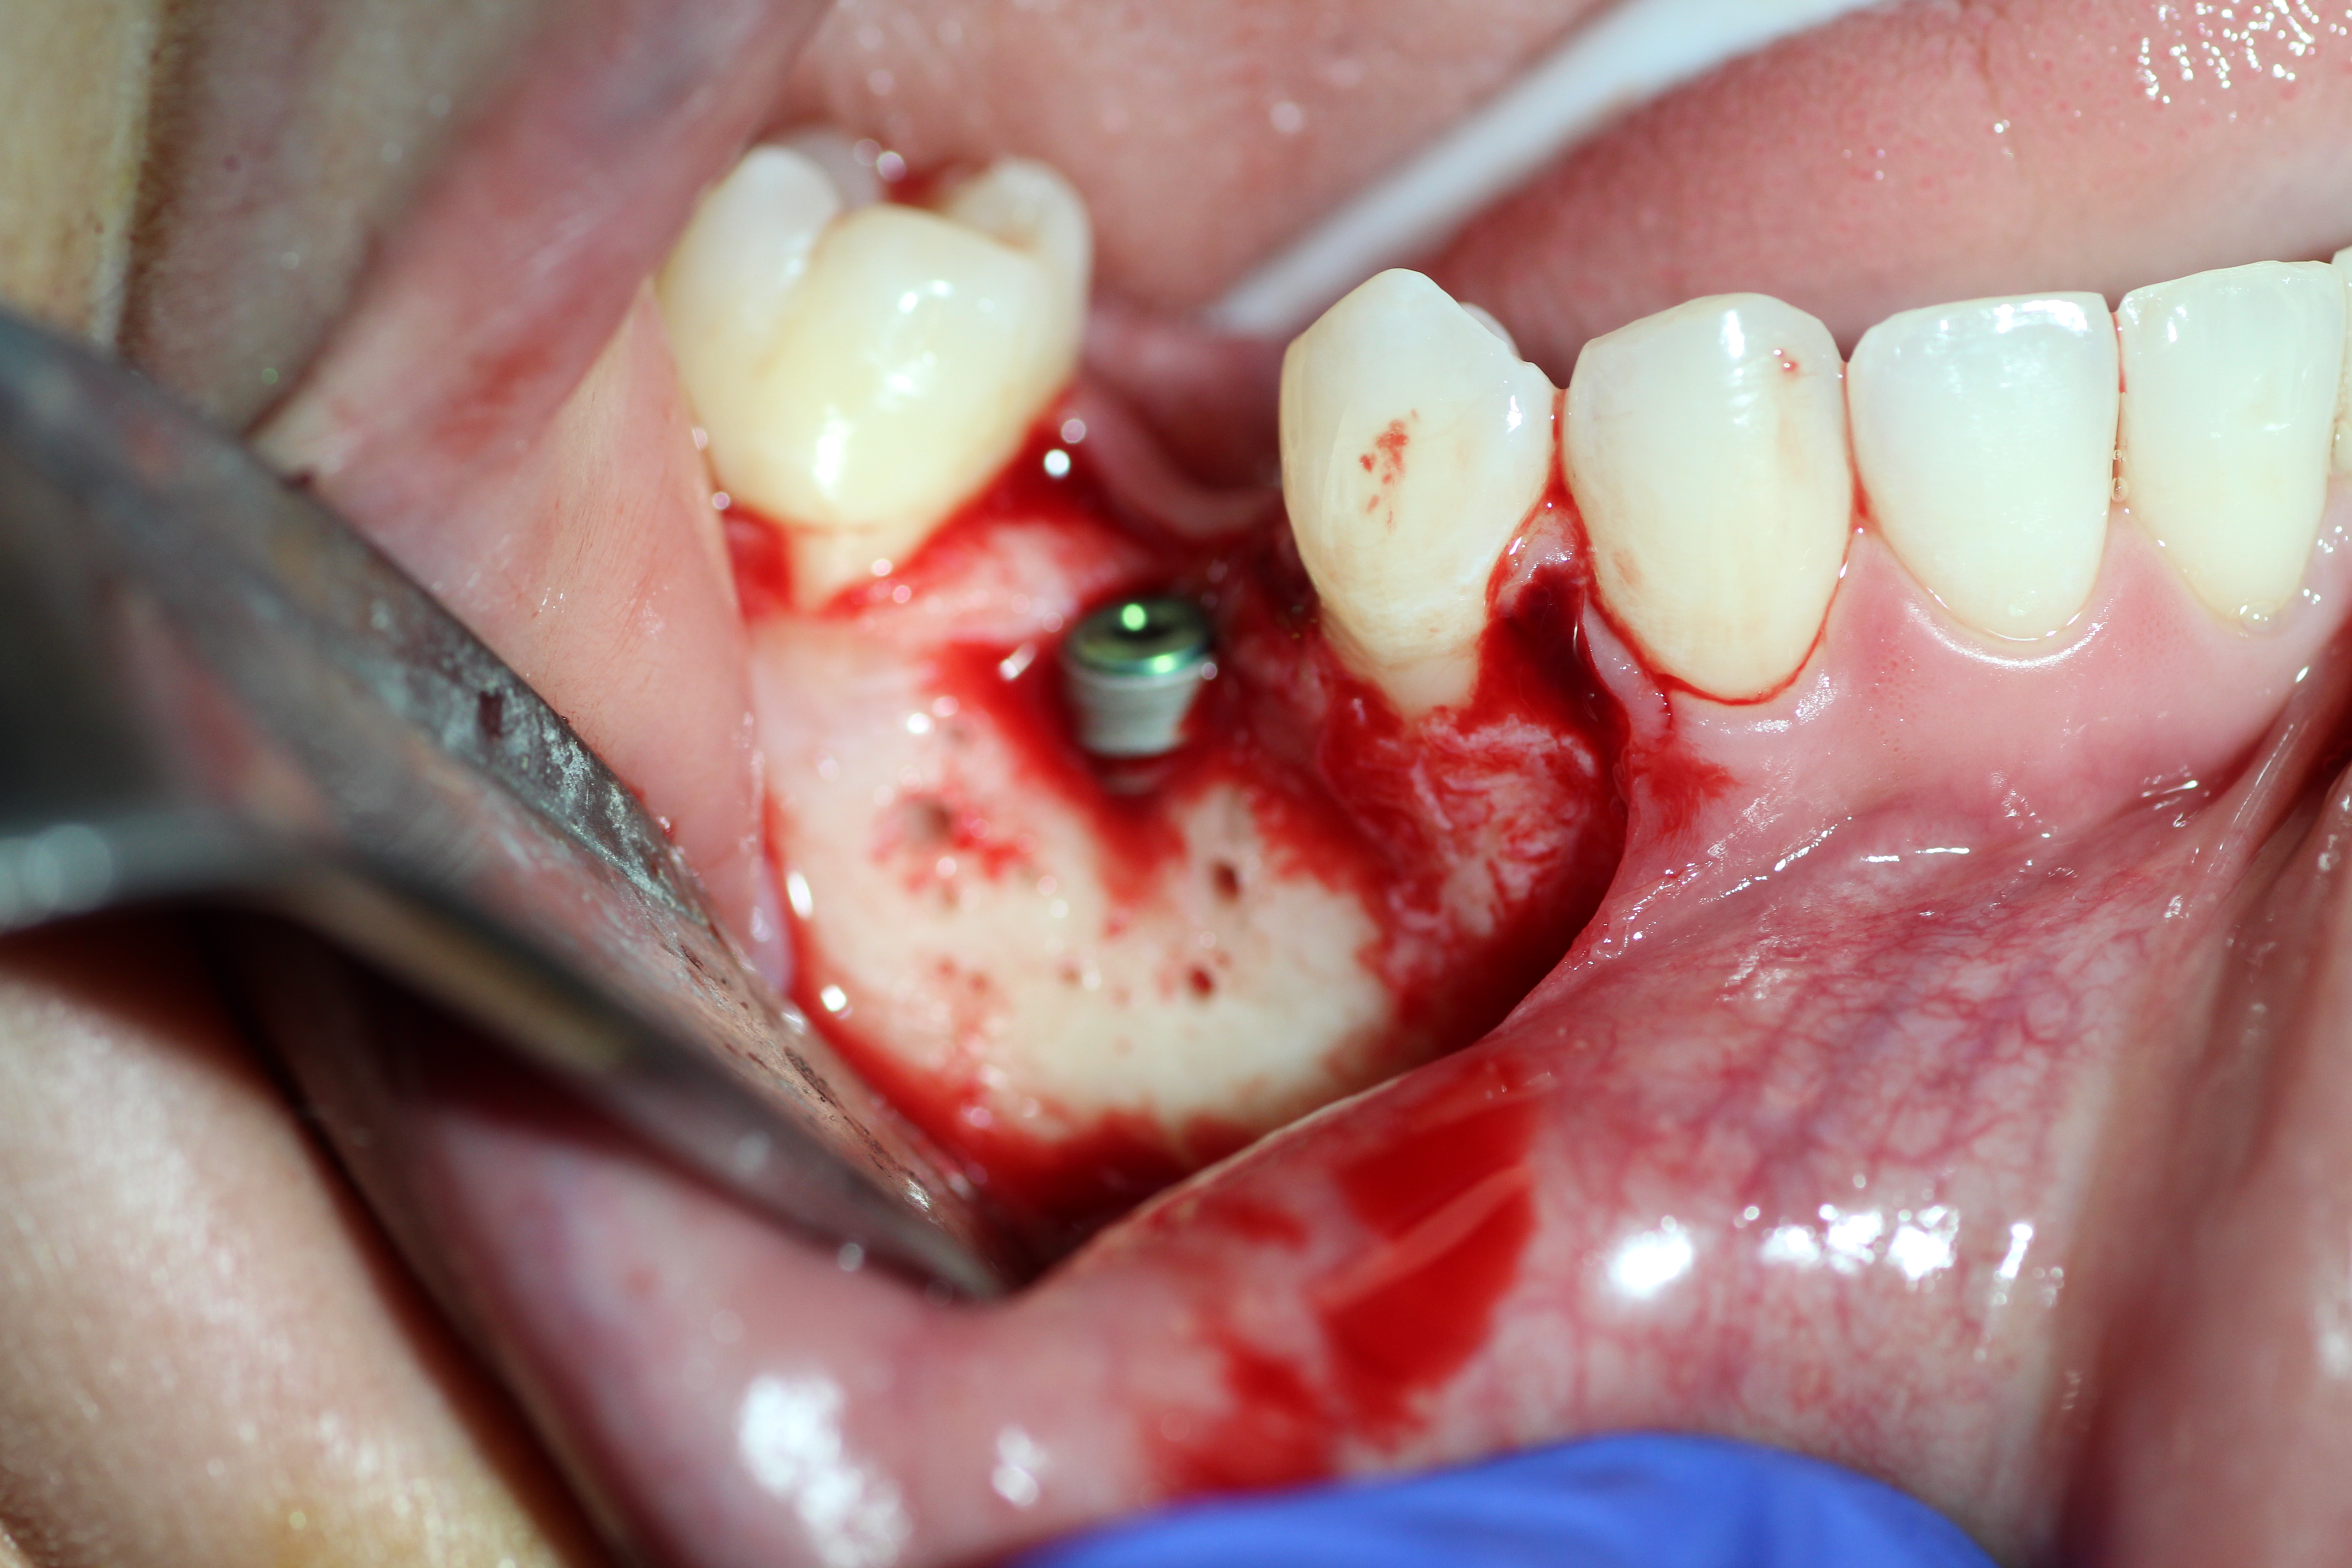

Case #2

Extraction and immediate implant placement with guided bone regeneration.

- Implant is in place.

- Bony defect measuring 3mm x 10 mm.

- Human cadaver particulated bonegraft packed into the defect followed by coverage with collagen membrane.